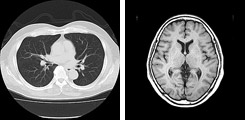

当院では一般撮影検査、及び透視装置ではフラットパネルを導入しており、被ばく線量低減に努めています。CT撮影検査でも被ばく低減ソフトを積極的に使用し、撮影条件の見直しも行っています。

- X線CT認定技師 2名(特定非営利活動法人 日本X線CT専門技師認定機構)

- 磁気共鳴専門技術者 2名(特定非営利活動法人 日本磁気共鳴専門技術者認定機構)